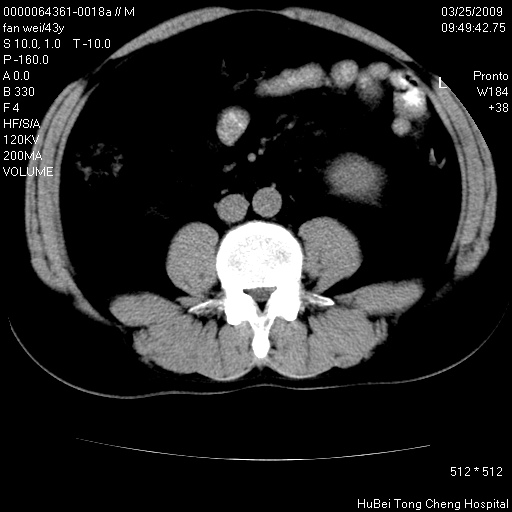

双肾ct轴位平扫+增强扫描(层厚10mm,螺距1.0,重建间隔10mm),图像如下:

多囊肾的影像诊断标准:有阳性家族史,年龄<30岁,单侧或双侧肾脏有两个肾囊肿;30~59岁,两侧肾脏各有两个肾囊肿;60岁以上,每侧肾脏有4个囊肿。敏感性和特异性达86%和80%。

此病例影像诊断符合,要结合家族史,腰痛、血尿、尿路感染史,有无高血压等综合判断,如无相应的临床症状,本身病变也无意义了(个人观点)

双侧多囊肾!

囊肿数得清,肾功能正常,考虑多发肾囊肿.另外,右肾后极突向肾周间隙的那个病灶是不是错构瘤,请楼主调窗看看.